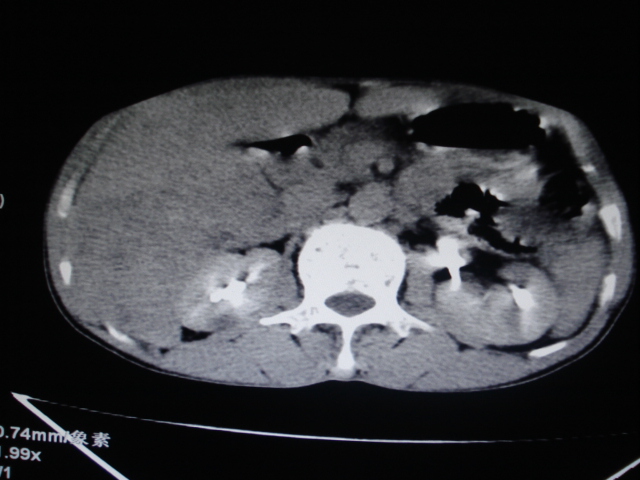

男性,62岁。肝右叶占位,平扫及增强如下,延迟期为15分钟扫描。